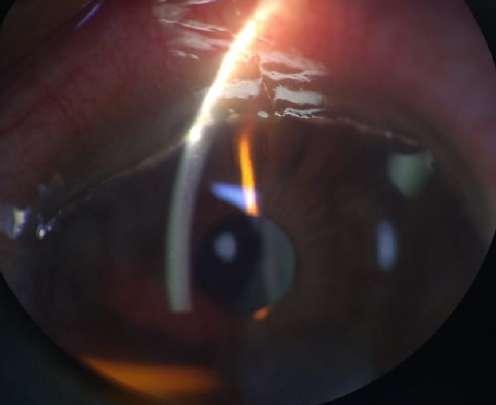

Caso aportado por Dr. Cristian Sanchez

Hombre 53 años con anteccedentes de facoemulsificación + implante de lente OD, consulta tras episodios de uveitis hipertensiva a repetición asociados a hifema del ojo derecho.

ü AV 0.7 OD

ü PIO OD: 28mmHg

ü BMC (Imagen A y B): Córna transparente, cámara anterior formada, Tyndall +, LIO in situ, transiluminación sectoriales del iris, iridotomías superior e inferior. Nevus conjuntival.

UVEÍTIS - GLAUCOMA - HIFEMA

8.C. SÍNDROME

A B

Caso

aportado por Dr. Cristian Sanchez

ü Gonioscopía (Imagen C): Ángulo abierto en en 270º, trabéculo con pigmento, SAP inferior

ü Fondo de ojo (Imagen D): Papila pálida con excavación 0.9. macula sana

ü El Sd. UGH es una complicación que puede aparecer en el post operatorio (precoz o tardío) luego de la implantación de un lente intraocular.

ü Se define clásicamente por la triada que su nombre comprende, aunque pueden aparecer formas incompletas.

ü La incidenccia se ha visto aumentada debido al incremento de la cirugía de cristalino, ya sea por catarata o con finalidad refractiva.

ü La patogenia se debe a la presión ejercida por los hápticos del lente intraocular (LIO) sobre el tejido uveal y puede presentarse en paciente con lentes en cámara anterior, sulcus o saco.

ü Sospechar en paciente pseudofáquico con episodios recurrentes de uveitis no filiada C D

8.C. SÍNDROME UVEÍTIS - GLAUCOMA - HIFEMA (UGH)

Sánchez C, Brosa H, Sanz S, Lillo J. Síndrome uveítis – glaucoma – Hipema: tres casos, tres causas. Hospital universitari de Bellvitge. Auditori Axa- Barcelona. 2016.